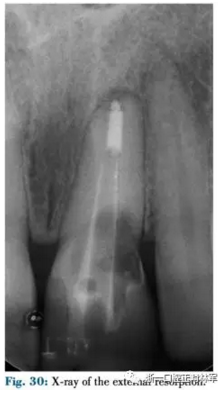

患者為一名41歲女性,由于創(chuàng)傷及外吸收導致左上中切牙骨缺損(圖30-32)。骨缺損使種植修復變得復雜需要GBR技術(圖33),因此需要大量的軟組織覆蓋薄膜,采用正畸牽引實現(xiàn)。